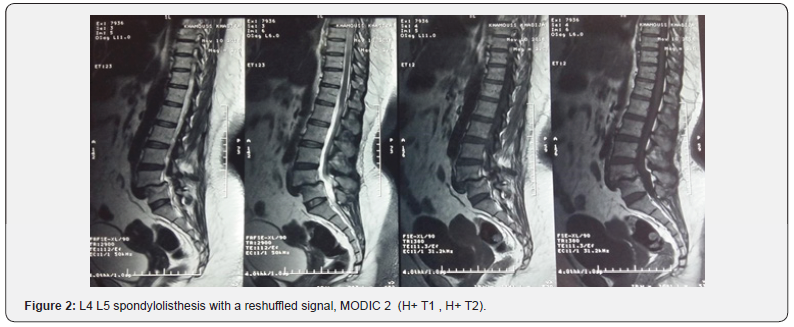

25 patients, 88% of whom were women, were included in our work, the average age was 54 years (34 to 70 years). At the time of the initial examination, all the patients had a severe mechanical low back pain which was rebellious to a well-managed medical treatment, 80% of the patients complained of radiculalgia, most often affecting the L5 and / or S1 territory. 14 patients had neurological claudications, 4 patients with motor neurological deficit; These disorders are in the form of functional impairment affecting the two lower limbs with an average rating of 3/5, 14 patients with sensory disorders : Hypoesthesia and Tingling of the lower limbs, and genito-sphincter disorders in two patients. The preoperative evaluation was based on the assessment of low back and radicular pain according to the visual analogue scale evaluation (VAS), the average score was 6 (4-9), and the patients’ quality of life evaluated according to the score d ‘Oswerstry (satisfaction index) with an average of 62 (40-80). The preoperative radiological analysis in our patients was based on x-rays of the lumbar spine (antero-posterior and lateral views) , dynamic images in flexion and extension (Figure 1), as well as magnetic resonance imaging. Isthmic lysis was the most frequent etiology of spondylolisthesis (56%), L5-S1 was its most frequent site (15 cases), the degree of slippage evaluated according to the MEYERDING classification showed that 56% of patients had a Grade I (Figure 1), and 44% had a Grade II. On MRI, stage I disc disease according to the MODIC classification was differentiated in 12 patients, stage II in 8 patients (Figure 2), 16 patients had an associated herniated disc, i.e. 64%, among the 25 cases, 14 patients had root compression i.e 56%.